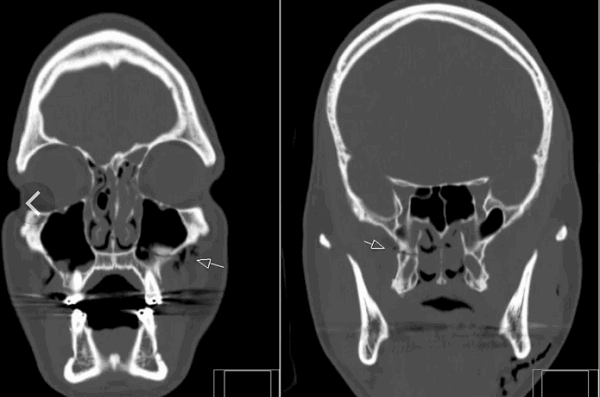

Кости черепа.

По МРТ можно определить перелом костей черепа. Кости свода плоские, видны на МРТ как темная тонкая полоска между кожей и мозговыми оболочками. При обследовании в разных проекциях можно обнаружить линии перелома. Однако они хорошо заметны и при обычной рентгенограмме. Она стоит дешевле и делается быстрее. Зато она не показывает, что происходит с мозгом и оболочками в результате травмы головы. На снимках МРТ можно определить, повреждены ли кроме костей мягкие структуры, есть ли гематомы, разрывы сосудов, очаги некроза, ушиб мозга. При травмах, которые сопровождаются неврологической симптоматикой, методом уточнения состояния головного мозга после перелома станет МРТ.

Перелом основания черепа, височных костей – всегда сложная травма. Она затрагивает множество структур, проходящих между костями, их отростками, внутри полостей. Наиболее полную картину после травмы черепа можно получить именно благодаря томографии на основе магнитного резонанса.

В травмпунктах и отделениях скорой помощи первым делом пациенту делают рентген. Если врач считает нужным, далее проводят МРТ или КТ. При подозрениях на внутричерепное кровоизлияние методом выбора в первые 6 – 8 часов после травмы будет КТ. В более поздние сроки определенные изменения будут видны и на снимках МРТ.